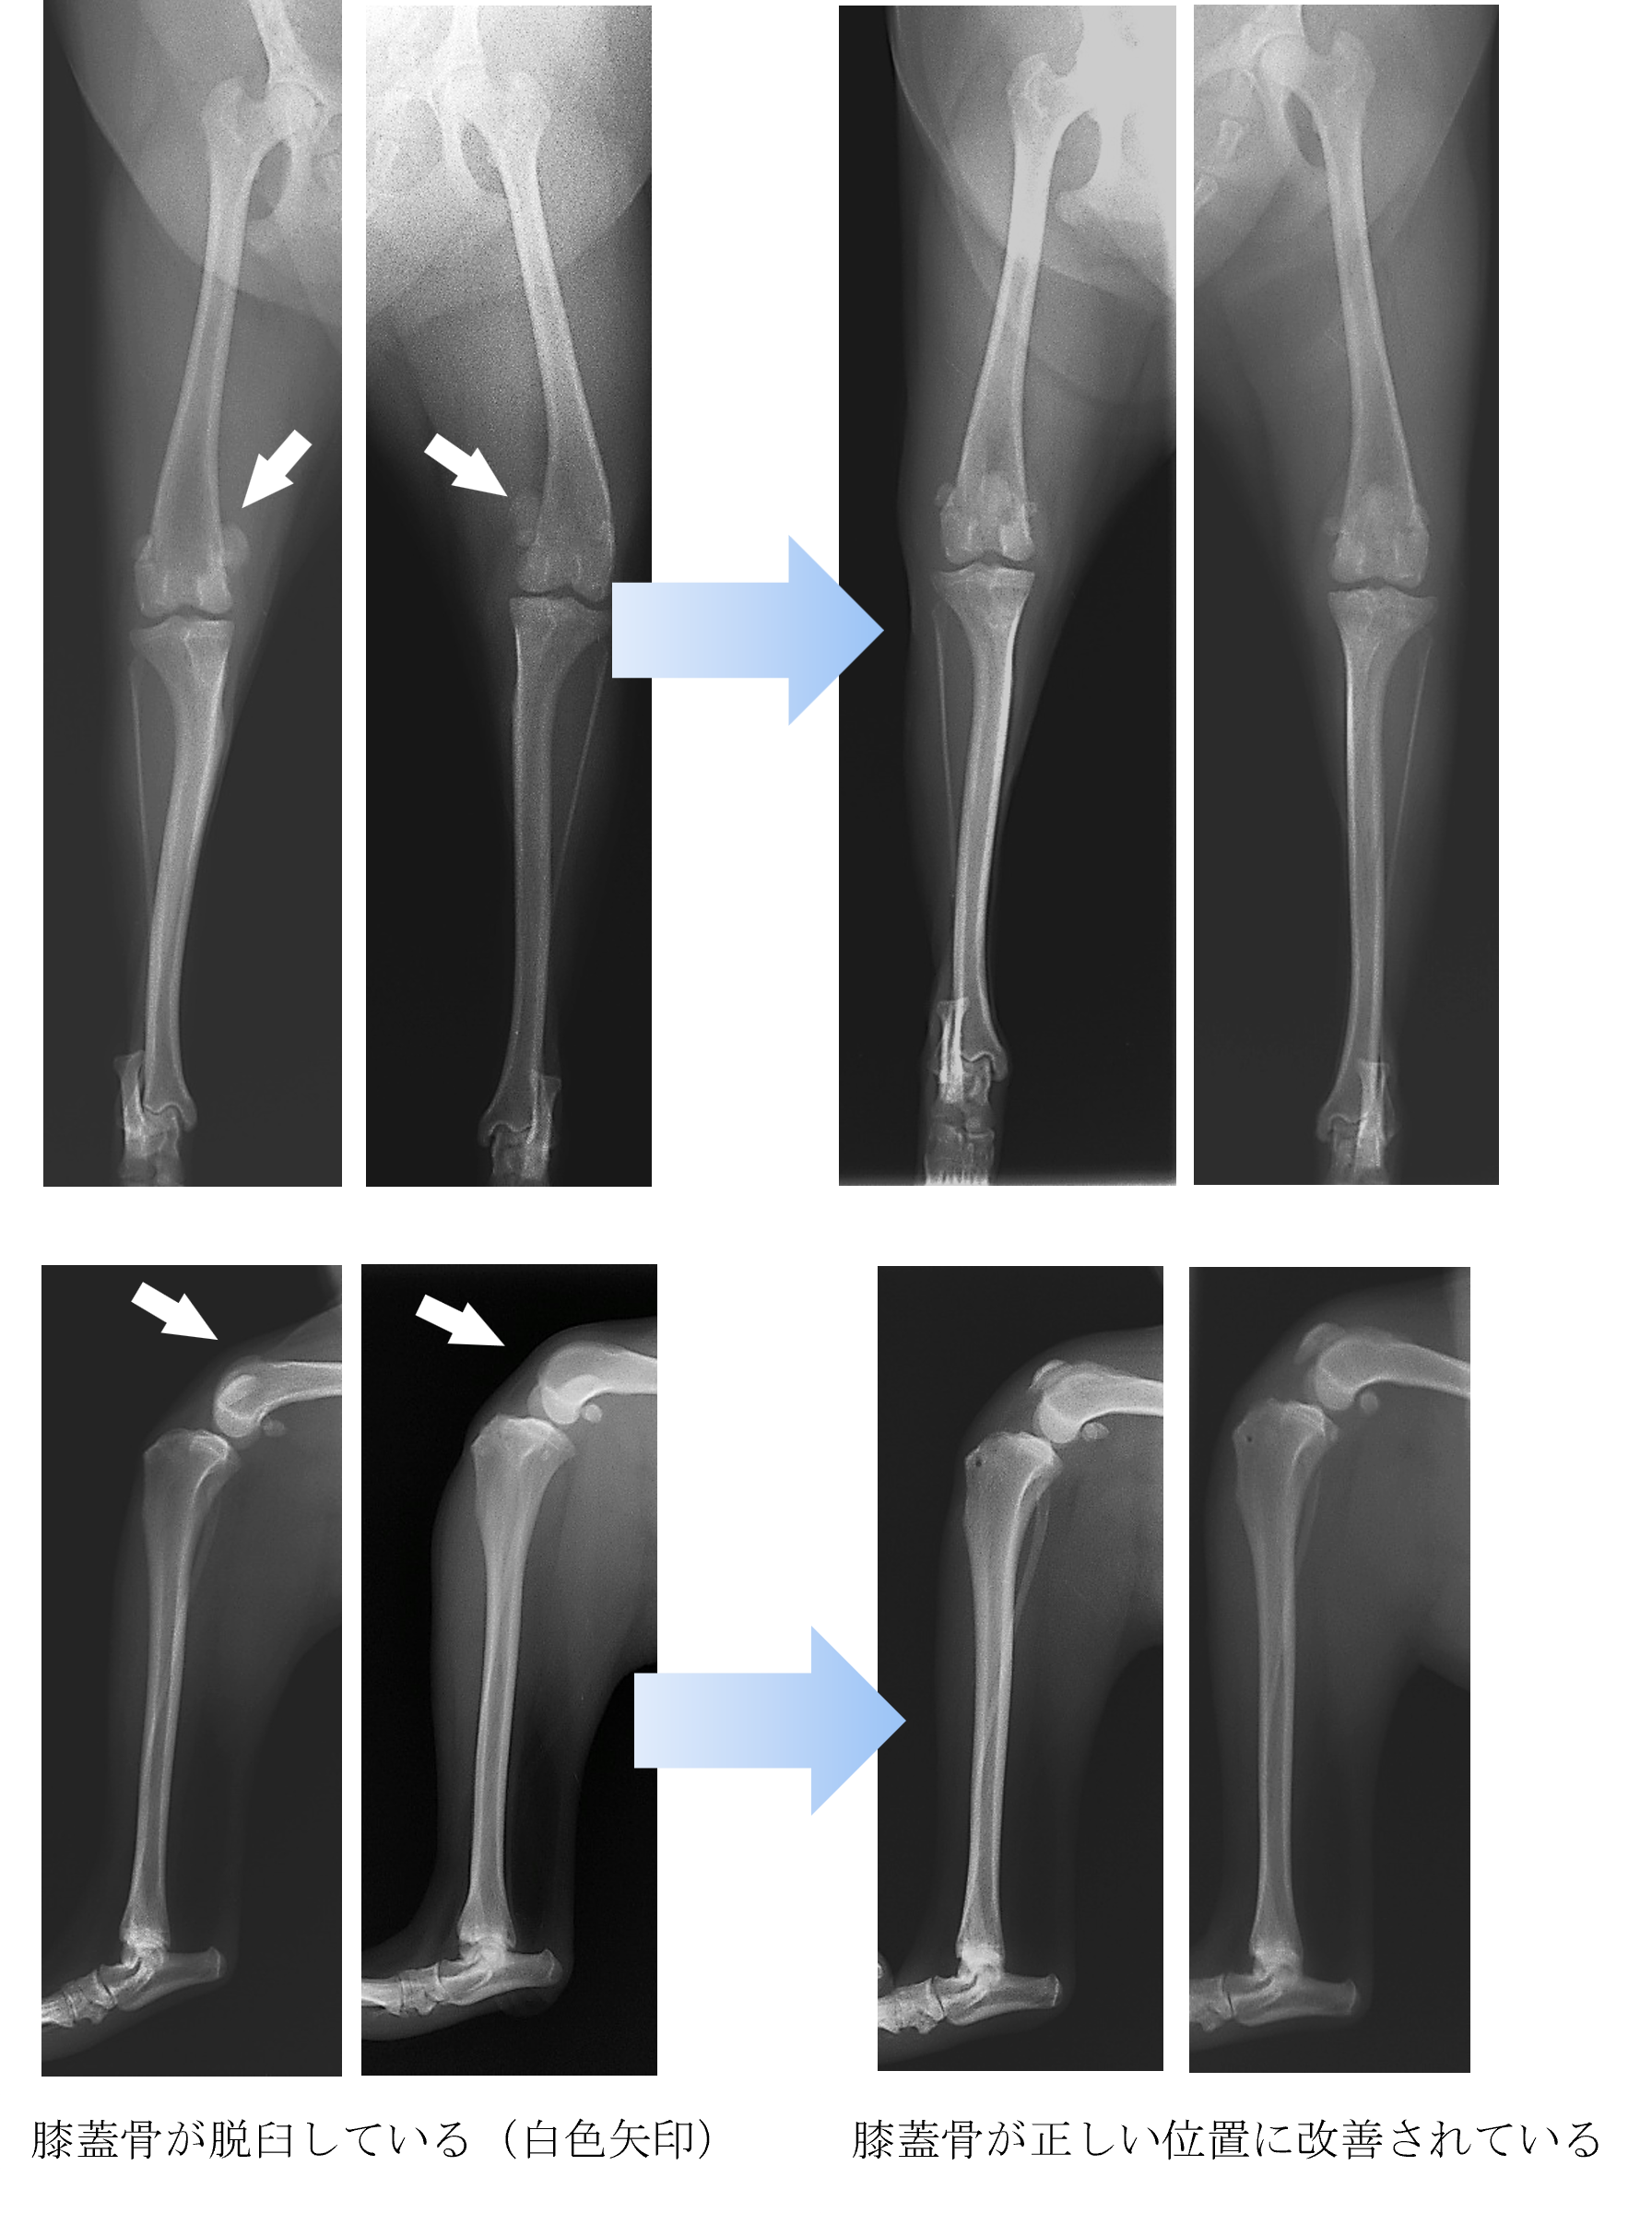

各種検査より、両側膝蓋骨(膝のお皿)脱臼(G4)と診断しました。

ご家族と相談して手術による膝蓋骨脱臼の整復を実施することになりました。

手術後は以前と同じように走ったり遊んだりすることができるようになりました。